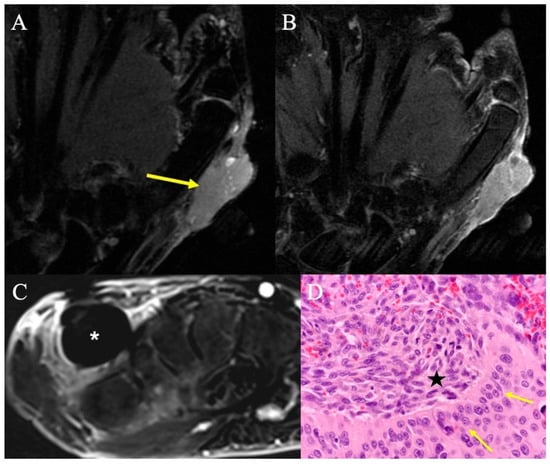

2.7.2. Imaging Appearance

- Walker, E.A.; Petscavage, J.M.; Brian, P.L.; Logie, C.I.; Montini, K.M.; Murphey, M.D. Imaging features of superficial and deep fibromatoses in the adult population. Sarcoma 2012, 2012, 215810. [Google Scholar] [CrossRef] [PubMed]

- Ramachandran, A.; Fox, T.; Wolfson, A.; Banks, J.; Subhawong, T.K. Superficial fibromatosis: MRI radiomics and T2 mapping correlate with treatment response. Magn Reson. Imaging 2021, 81, 53–59. [Google Scholar] [CrossRef] [PubMed]